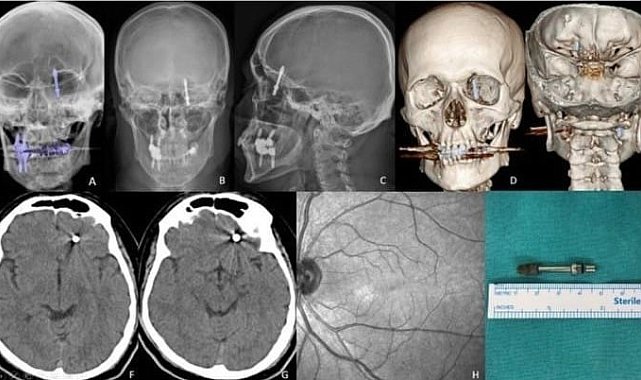

BURSA (İHA) – Bursa'da diş tedavisi için gittiği özel klinikte yaptırdığı implant işlemi, fabrika işçisi Ramazan Yılmaz'ın (40) hayatını kabusa çevirdi. İddiaya göre, doktorun hatalı müdahalesi sonucu implant vidası çene kemiğini delip kafatasına saplandı. Ölümle burun buruna gelen talihsiz adam, saatler süren ameliyatla hayata tutundu. Ancak aradan geçen 2 yıla rağmen ne adalet yerini buldu, ne de sorumlular cezalandırıldı. Hatalı bulunan diş hekimine ise sadece 10 muayene ücreti ceza verildi.Nilüfer ilçesinde özel bir diş kliniğinde muayene olan Yılmaz'a, dişlerinin sallandığı gerekçesiyle implant tedavisi önerildi. Ancak iddiaya göre, doktor A.D.'nin hatalı müdahalesi sonucu implant vidası çene kemiğini delip kafatasına saplandı.Baygınlık geçiren Yılmaz, kliniğin kendi aracıyla hastaneye kaldırıldı. Tomografi çekiminde vidanın beynine kadar ilerlediği ortaya çıktı. Acil ameliyata alınan talihsiz adam, saatler süren operasyonla ölümden döndü."İki yıldır mahkeme tarihi bile verilmedi"Olayın ardından büyük bir travma yaşayan Ramazan Yılmaz, hem sağlığını hem işini kaybetti. Doktordan ödediği ücretin iadesini isteyen Yılmaz, ret cevabı alınca hukuk mücadelesi başlattı. Ancak iki yıldır dosyasında tek bir duruşma günü bile verilmedi.Adli tıp raporunun dosyaya eklenmediğini söyleyen Yılmaz, "Beynime implant saplandı ama kimse sorumluluk almıyor. Başhekime kadar gittim, hâlâ bir muhatap bulamadım" diyerek yaşadığı çaresizliği anlattı.Diş hekimine sadece 10 muayene ücreti cezasıBursa Diş Hekimleri Odası, olayla ilgili doktor A.D.'ye yalnızca 10 muayene ücreti tutarında para cezası verdi. Bu kararı "insan hayatını hiçe saymak" olarak nitelendiren Yılmaz, "İnsan hayatı 5 bin lira mı?" sözleriyle tepki gösterdi.Birliğe de dava açtığını belirten Yılmaz, "Adaletin tecelli etmesini bekliyorum. Raporlar bir şekilde engelleniyor. İnsan hayatına mal olacak bir hataya imza atıldı, ama kimse hesap vermiyor." dedi."Kamu vicdanı bu kararı bekliyor"Sağlık Bakanlığı ve adli makamların sessizliğinden dert yanan Yılmaz, "İki yıldır bekliyorum. Adaletin yerini bulmasını, sorumluların cezalandırılmasını istiyorum. Bu sadece benim değil, tüm toplumun meselesi. Böyle hatalar cezasız kalmamalı" diyerek çağrıda bulundu.